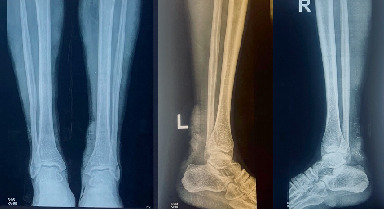

Introduction: Interpersonal violence victims account for a sizable proportion of trauma cases encountered in South African trauma centers. Open Achilles tendon injuries are more prevalent in male patients, accounting for a high number of all cases. Case Report: A 45-year-old male was brought in a trauma casualty by a paramedic after being referred by a local clinic in severe pain on both ankles, unable to walk or stand, and dressed bilaterally with blood stains. On examination, he demonstrated the triad of Achilles tendon injuries, including Matle's sign, Thompson's test, and a gap on palpation. A surgical operation was performed within 24 h of the patient's admission. Conclusion: This case report is aimed at increasing awareness of a rare case that presented with open bilateral Achilles tendon injuries associated with an alleged assault and received a successful surgical treatment without a skin complication.

Abstract Image